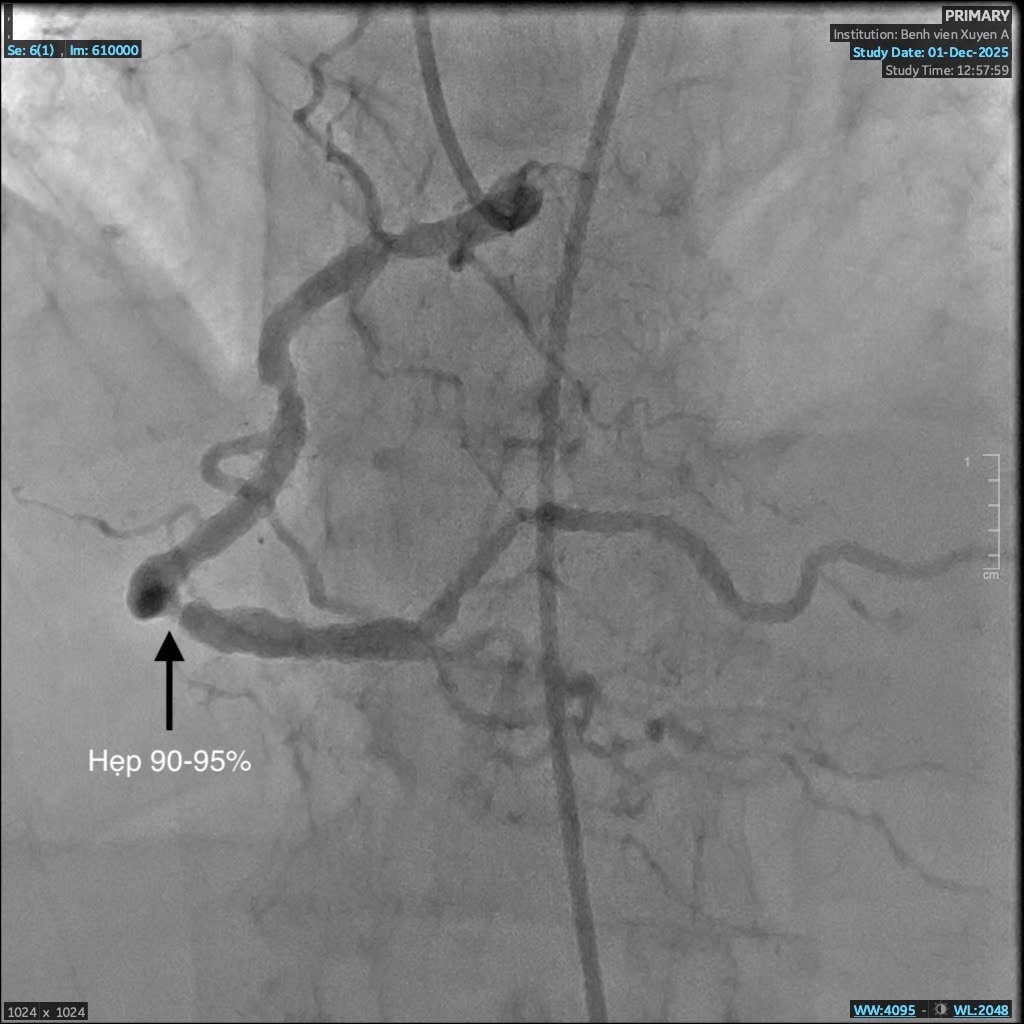

Mạch máu trước can thiệp

Mạch máu trước can thiệp hẹp đến 95%

Ngay khi tiếp nhận, các bác sĩ khoa Cấp Cứu đã thăm khám và ban đầu xác định bệnh nhân bị phù phổi cấp. Người bệnh được chuyển lên khoa Hồi Sức Tích Cực để điều trị ổn định tình trạng suy hô hấp, sau đó chuyển bệnh nhân lên phòng DSA chụp mạch máu nuôi tim kiểm tra tình trạng tim mạch. Kết quả chụp động mạch vành phát hiện bà C. bị hẹp nặng ba nhánh mạch vành, rơi vào nguy kịch nhồi máu cơ tim. Đây là nguyên nhân chính khiến bà khó thở, đau nặng ngực.

BS. Giản Tư Trí – khoa Can Thiệp Tim Mạch BVĐK Xuyên Á cho biết: “Bệnh nhân C. có tiền căn hen phế quản vào viện trong tình trạng suy hô hấp, việc chẩn đoán gặp nhiều khó khăn. Trong quá trình can thiệp, dưới hướng dẫn của hệ thống số hóa xóa nền DSA, ê-kíp nhận thấy mạch vành của bệnh nhân bị vôi hóa nhiều do đái tháo đường, suy thận lâu năm. Vôi hóa là “kẻ thù” của can thiệp mạch vành, gây khó khăn cho việc nong và đặt stent, thậm chí khiến việc can thiệp thất bại. Nhưng với sự tỉ mỉ và kinh nghiệm xử trí nhiều ca đặt stent phức tạp trước đó, các bác sĩ khoa Can Thiệp Tim Mạch đã vượt qua thách thức và đặt stent thành công, tái thông mạch máu nuôi tim, cứu bà C. qua cơn nguy kịch.”